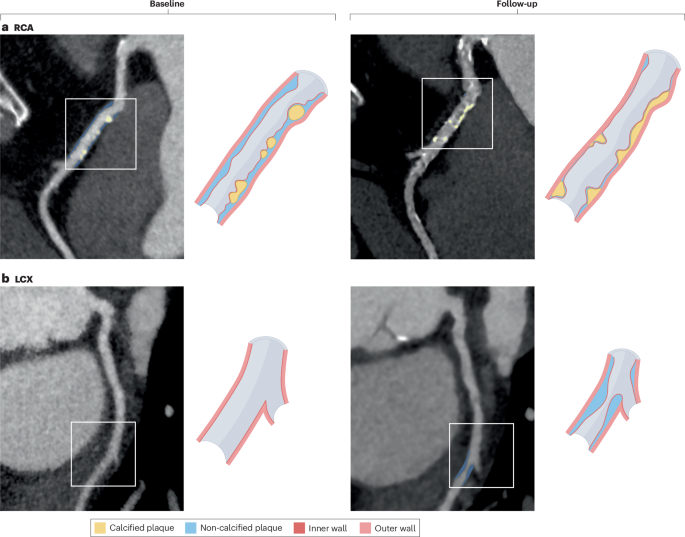

冠状动脉CT血管造影被广泛应用,仅在欧洲,每年估计有220万例稳定胸痛患者接受了冠状动脉CT血管造影。同时,人工智能和机器学习有望通过提高可靠性和速度来改变冠状动脉粥样硬化斑块的评估。然而,对于如何使用冠状动脉粥样硬化成像生物标志物来个性化推荐药物治疗,人们知之甚少。本共识声明来自定量心血管成像(QCI)研究小组,概述了在2024年9月第三次国际QCI研究小组会议后进行的三步德尔菲过程中得出的关键建议。来自不同心血管成像领域的专家一致同意使用年龄调整和性别调整的百分位曲线,基于来自DISCHARGE和SCOT-HEART试验的冠状动脉斑块数据。解决了两个关键问题:需要利用人工智能和机器学习工具的可靠性和精确性,并在个性化斑块分析的基础上定制治疗。QCI研究小组建议,任何动脉粥样硬化斑块的存在都应推荐药物治疗,而斑块总体积的70百分位数需要高强度治疗。这些建议的目的是为未来的试验奠定基础,并释放冠状动脉CT血管造影的潜力,以改善全球患者的预后。

Coronary CT angiography is widely implemented, with an estimated 2.2 million procedures in patients with stable chest pain every year in Europe alone. In parallel, artificial intelligence and machine learning are poised to transform coronary atherosclerotic plaque evaluation by improving reliability and speed. However, little is known about how to use coronary atherosclerosis imaging biomarkers to individualize recommendations for medical treatment. This Consensus Statement from the Quantitative Cardiovascular Imaging (QCI) Study Group outlines key recommendations derived from a three-step Delphi process that took place after the third international QCI Study Group meeting in September 2024. Experts from various fields of cardiovascular imaging agreed on the use of age-adjusted and gender-adjusted percentile curves, based on coronary plaque data from the DISCHARGE and SCOT-HEART trials. Two key issues were addressed: the need to harness the reliability and precision of artificial intelligence and machine learning tools and to tailor treatment on the basis of individualized plaque analysis. The QCI Study Group recommends that the presence of any atherosclerotic plaque should lead to a recommendation of pharmacological treatment, whereas the 70th percentile of total plaque volume warrants high-intensity treatment. The aim of these recommendations is to lay the groundwork for future trials and to unlock the potential of coronary CT angiography to improve patient outcomes globally.